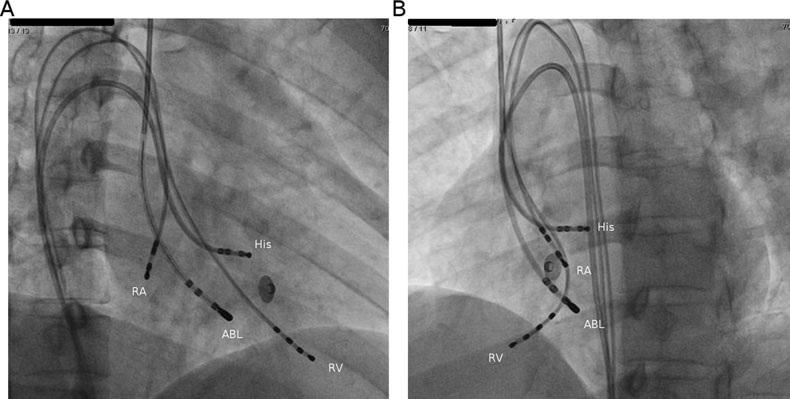

Substrate - Atriotomy

flutter3.jpg

dp.jpg